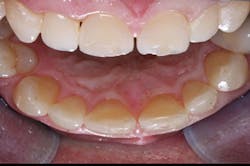

Intact lingual surfaces-If the lingual surfaces are worn through to dentin or carious, veneers are not indicated, and crowns should be placed. Lingual surfaces should be intact for veneers (figures 1, 2).

Figure 1: Two central incisors to be restored show deep facial restorations extending onto the lingual surfaces with a diastema present. These teeth would probably be better treated with crowns.